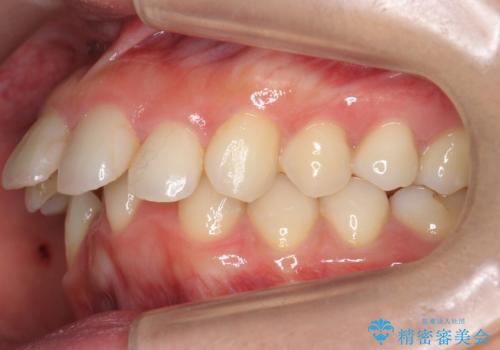

出っ歯 下の歯のガタガタ 下の前歯のみ1本抜歯 マウスピースで1年

- 出っ歯を主訴に来院。

古典的な方法では4本抜歯した後、ワイヤー矯正という方法も選択肢には上がりましたが、下の前歯を1本だけ抜くことにし、マウスピースで短期間で治療を終わらせるようにしました。

治療も比較的短期間で終わり、大変喜んでいただきました。

下の前歯を1本抜くと上下の正中はあいませんが、ほとんど目立ちません。